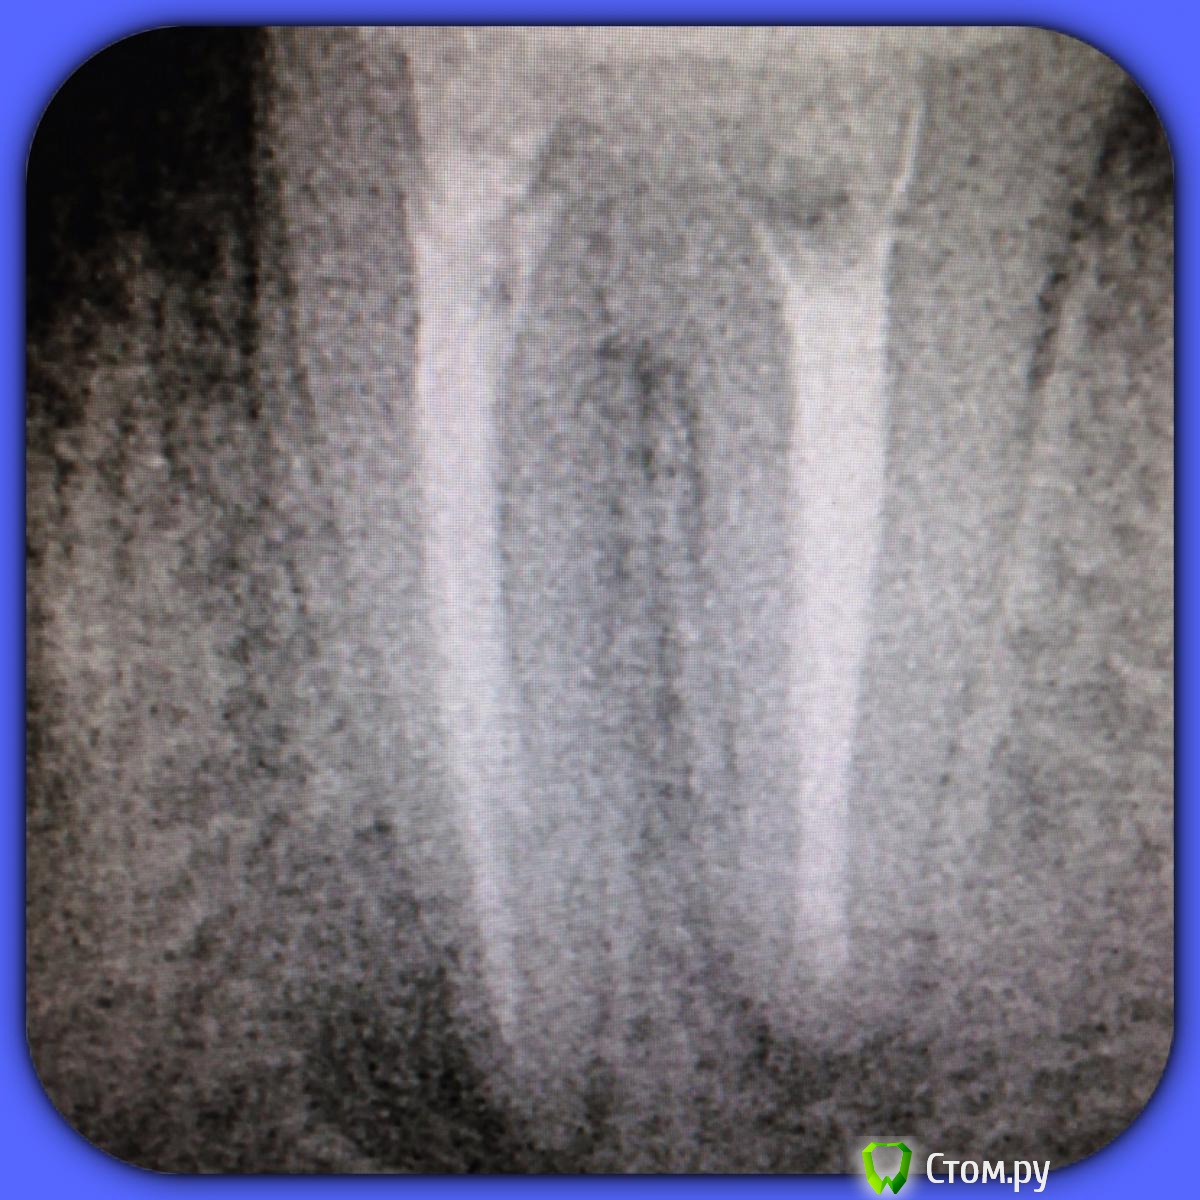

SSTi Опубликовано 18 июня, 2014 Автор Поделиться Опубликовано 18 июня, 2014 Вот что вышло. Пробился до куда смог. Вымыл все очень интенсивно и долго. И запломбировал. Зуб после прошлого визита не болел Ссылка на комментарий

SSTi Опубликовано 18 июня, 2014 Автор Поделиться Опубликовано 18 июня, 2014 Я не считаю это успехом. Щечный пробил конкчно немного, но не до апекса. Зуб под наблюдение...Но думаю лучше так, чем перфо или сломать файл Ссылка на комментарий